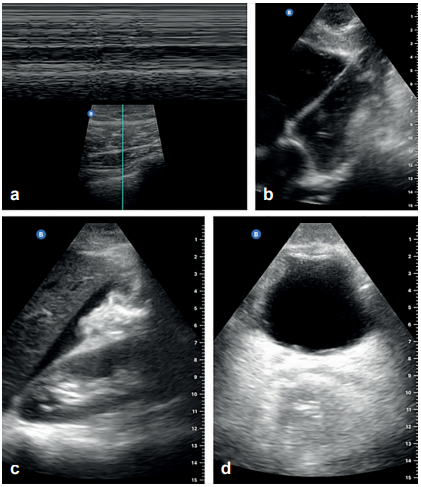

A total of 46 patients were included, with a mean age of 31.2 ± 13.8 years, 87.4% (n=39) were male. The main mechanism of trauma was penetrating (n=32; 69.5%), 93.4% (n=43) were taken to the operating room, mainly performing emergency laparotomy (n=24; 52.1%); 37 (80.4%) patients had positive E-FAST (Figure 1), 97% (n=35) were found to be true positive, based on intraoperative findings (only two were false positive). Of the nine (19.5%) patients with negative E-FAST, five underwent surgery, with three having positive findings of free cavity fluid (false negative) (Table 1). In comparison to the imaging and intraoperative findings, the sensitivity, specificity, PPV, NPV were found to be 92.1%, 75%, 94.6% and 66.6%, respectively. The PVR was 3.68, while the NPV was 0.10. The accuracy was found to be 89%.